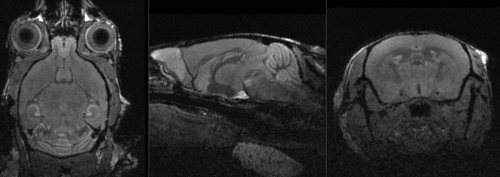

Registration Results

shown are, from left to right, panels of axial, sagittal and coronal views.

original brain in non-RAS orientation original, not RAS

original brain in proper RAS orientation original,after reorientation into RAS

Aim is to register the two brains of control mice to eachother. The original images have their header orientation info in a nonstandard form. As a consequence the image loads with sagittal and axial views switched. To fix we create a reorientation transformAlso the target image content is of low intensity and small compared to the surrounding tissue, making masking essential. We will first correct the orientation issue and apply intensity bias correction, then build two masks for registration, and finally co-register the two images in two steps via affine and non-rigid BSpline transforms.

• reference/fixed MRI: 0.1 x 0.1 x 0.1 mm, 192 x 256 x 192

• moving MRI: 0.1 x 0.1 x 0.1 mm, 192 x 256 x 192